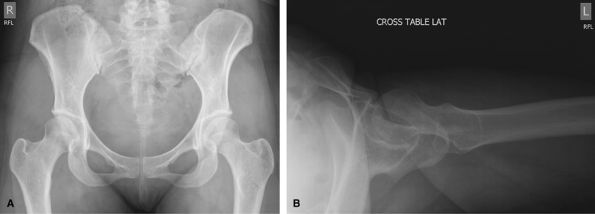

Include Both Hips on Image

Good initial screening test for acute trauma. Good for

ill defined pain or metastatic search. Consider CT for full assessment

of pelvic trauma.

![]() |

Figure 37 AP pelvis.

Hips

Trauma, Acute Injury. AP pelvis and a crosstable lateral to assess for hip pain localized to the 1 side of the pelvis/hip.

Figure 38 (A) AP pelvis. (B) Inferosuperior lateral to include proximal femur and hip joint for unilateral injury.

Nontrauma, Chronic Injury.

The crosstable lateral is replaced by a frog lateral. The frog leg can

be bilateral or unilateral depending on the pain. MRI is an excellent

way to assess hip pain if the radiographs show only minimal abnormality.

MRI arthrogram can give useful additional information about the labrum.

Figure 39 (A) AP pelvis. (B) Bilateral frog leg. (C) or Frog-leg lateral of affected hip.